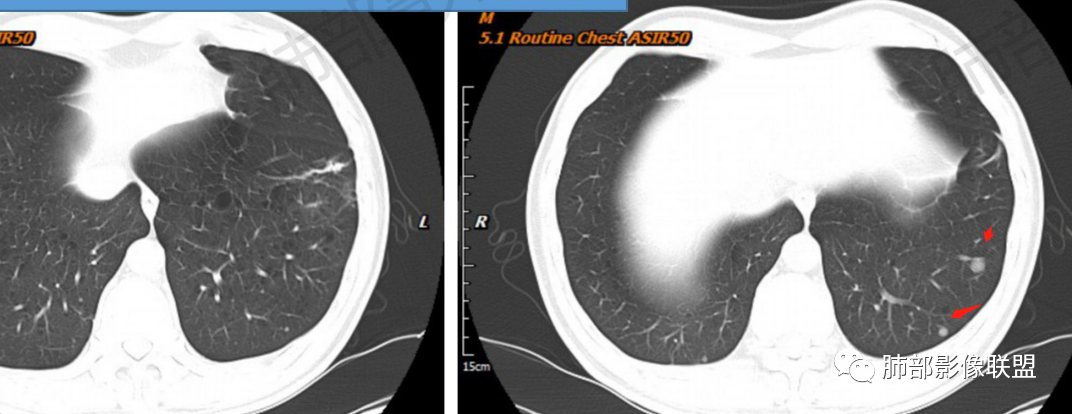

一切∮随缘:左肺下叶不规则肿块,边缘光滑,平直,局部彭隆,分叶,近端支气管堵塞,远端与胸膜相贴,平扫密度尚均匀,增强后不均匀强化,内部可见低密度坏死,胸膜下多发肺气肿,伴双肺散在光滑小结节,实验室肿瘤标志物高,考虑恶性:神经内分泌癌(大细胞),腺癌,鳞癌。

琦遇:恶性没有问题,肺气肿底子、病灶分叶、少许毛刺、叶间胸膜凹陷、部分边缘可见清晰的GGO、胸膜牵拉凹陷、局部胸水、近端支气管截断、部分支气管被推移、占位效应明显、强化特点为不均匀强化、内部有少许沼泽样低强化区,强化部分轻中强化为主、余肺可见转移性结节、左肺上叶似为囊腔型腺癌一枚,肿瘤标志物提示非小、神经内分泌,综合分析考虑大神泌、腺癌、腺鳞癌、鳞癌  同时左肺上叶囊腔型腺癌  肺转移

飞鹰行动:中年人,男性,胸疼入院,左肺下叶占位,张力较高,边界可见分叶,局部可见明显收缩性改变,增强病灶内部有延迟强化表现,考虑恶性病变,大细胞癌伴肺内转移或者囊腔样腺癌伴转移。

蕊:中老年男性,吸烟史,肺气肿背景,左肺上叶类圆形肿块影,边界清晰,边缘凹凸不平,有分叶,支气管进入阻断,临近胸膜栽赃,整体病灶膨隆,局部周围可以清晰ggo,临近叶间裂内凹,轻度强化,并可见多个低密度区,坏死可能,界线不清;肺内多结节,边缘光滑,考虑恶性伴转移,鳞癌、腺癌

傅昌瑜:中老年男性,肺气肿背景,右胸背疼痛1周。CEA、NSE、CYFRA—211升高。左上肺混合磨玻璃结节,内见较多空泡和扩张支气管。左下肺胸膜下肿块,边缘较光滑,深分叶,似有血管进入,与支气管关系不清,内见不均匀强化,见沼泽地样坏死,有胸膜栽赃。另两肺多发圆形小结节。考虑恶性并肺内转移,多原发可能性大,左上肺腺癌,左下肺病理难以判断,小细胞癌?鳞癌?

小锁:中老年男性,肺气肿背景,右胸背疼痛1周。CEA、NSE、CYFRA—211升高。左上肺混合磨玻璃结节,边界清楚,内见较多空泡。左下肺肿块,边缘清楚,深分叶,有血管和支气管进入,胸膜凹陷。另两肺多发圆形小结节。考虑双发原位癌,左上肺腺癌,左下肺大神泌或腺鳞癌可能,肺内转移。

蓝天白云:中年男性,肺气肿背景,左肺下叶肿块,边缘膨隆,有分叶,内有湖泊样坏死,有轻中度强化,局部胸膜栽赃,收缩力不强,周围见肺气肿征象。左肺上叶混合磨玻璃影,边界清楚,考虑都是恶性,左上肺iac,左下肺腺鳞癌,或大细胞肺癌可能。两肺多发结节,考虑转移

毛勤香:老年男性,肺气肿背景,左肺下叶肿块,分叶,边缘光滑,土豆块样,细支气管闭塞,增强轻度不均匀强化,似有坏死,左肺另见多发结节,淋巴结未见明显肿大,恶性确定,吸烟史,鳞癌破坏力强,侵袭力差,多原发的一般很少多于3个,故排后,首先考虑神经内分泌癌,局部血管穿行,鉴别淋巴瘤

周太狼:中年男性,吸烟、高血压史,肿瘤指标升高,肺气肿背景下,左肺下叶肿块影,分叶、膨隆、未跨叶裂,支气管截断,不均匀强化。另双肺多发结节及磨玻璃影,左肺上叶混合磨玻璃,内可见多发空泡影。整体考虑恶性,肺癌伴肺内转移,左下肺鳞癌?神经内分泌癌?左肺上叶囊腔腺癌?